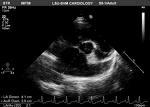

Additionally, imaging of the valve from multiple views is recommended with particular attention to motion of leaflets or occluder, presence of calcification on the leaflets or abnormal echo density on the various components of the prosthesis, and valve sewing ring integrity and motion.

The guidelines stress the importance of Doppler echocardiography of the valve to evaluate some of the following parameters: